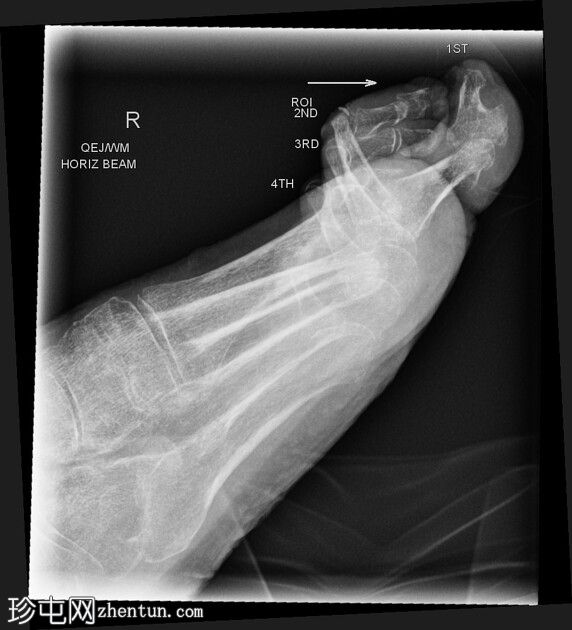

侧位

侧位片显示第二近节趾骨头背侧皮质透亮,符合骨髓炎表现。